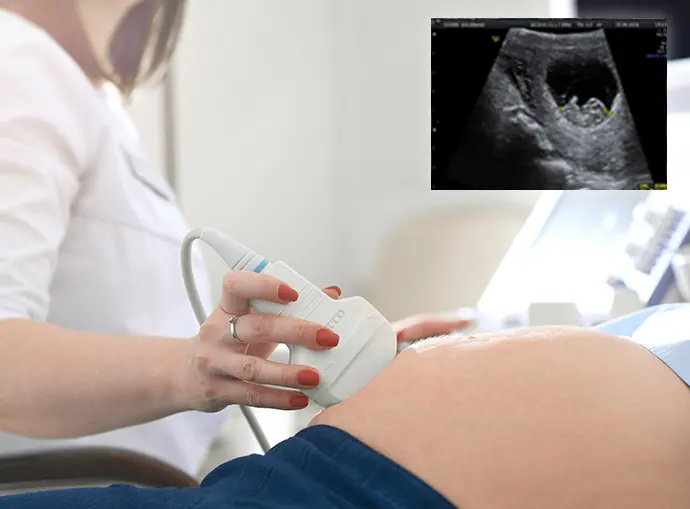

The EarlyReassure™ scan is an early pregnancy viability scan specifically designed for expectant parents who are seeking reassurance prior to attending their first NHS scan, especially in cases of vaginal bleeding to confirm that the pregnancy is viable. The EarlyReassure™ scan is also beneficial to those who are keen to establish the gestation age of their baby and to assist with the scheduling of their NHS Dual Screening Scan (Dating & NT), elements of which must be conducted prior to 14 weeks. It is also beneficial for IVF pregnancies, providing development assessment and reassurance.

During the scan, your fully-qualified obstetric sonographer will check your uterus and ovaries to exclude ectopic pregnancy and to measure baby's crown-to-rump length (CRL - head to bottom) to verify gestation age, providing an initial estimated delivery date (EDD). We will also check the yolk sac which is baby’s source of food prior to the formation of the placenta, and seek to provide visual confirmation of heartbeat and movement together with confirmation of the number of babies you are carrying. All of this information will be documented in the form of a digital Foetal Assessment Report.

Your reassurance scan will be conducted using an abdominal ultrasound probe (external on the abdomen), and it is important to recognise that imagery obtained is derived from the reflection of sound waves passing through your abdomen creating the visual image. From 6 weeks gestation your baby is likely to measure approximately 5mm in length; as such, the level of diagnostic evaluation and visibility achievable should you attend this type of scan as early as 6 weeks can differ greatly between clients. This is especially true in cases of a high BMI, which can result in poor image resolution and possibly lead to an inconclusive evaluation.

Scan Time & Baby’s Safety